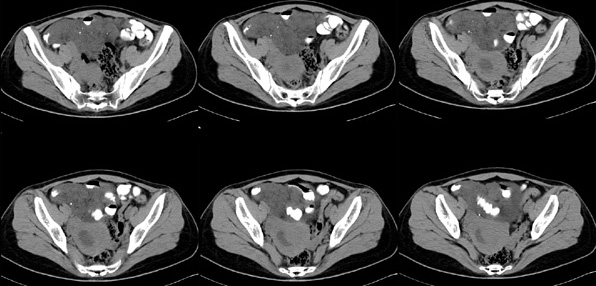

女性,28岁,停经3月,腹部膨隆1月,产前检查发现腹部占位

{肿块中心ct值27hu,增强后,动脉期、门脉期均无明显强化)

患者手术病理:腹腔囊性淋巴管瘤,象这样充满整个腹腔的的确很少见